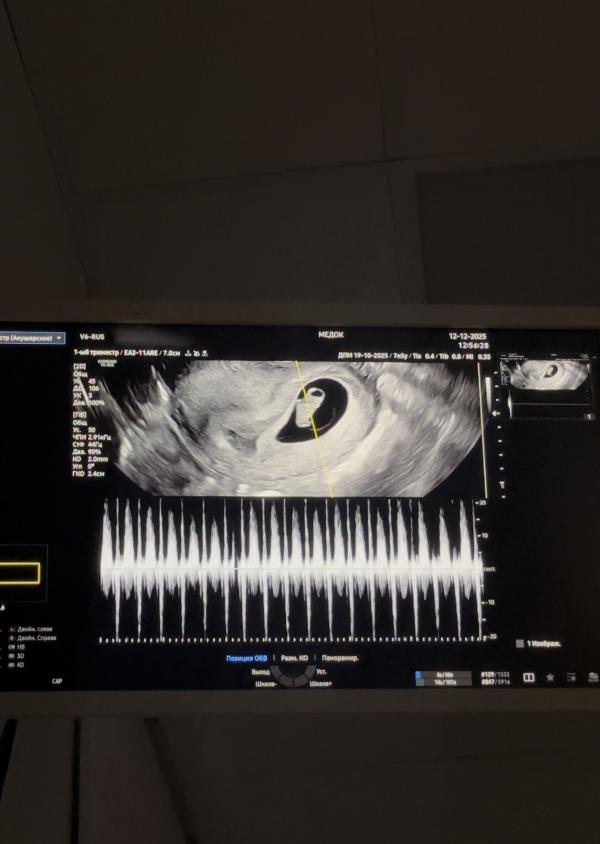

Съездила к своему гинекологу, сдала мазки, послушали сердечко💔

@irinka.stylistka, а все поняла, ну надеюсь что так🥹🥹 ну вчера по узи все хорошо было , но еще схожу, очень переживаю